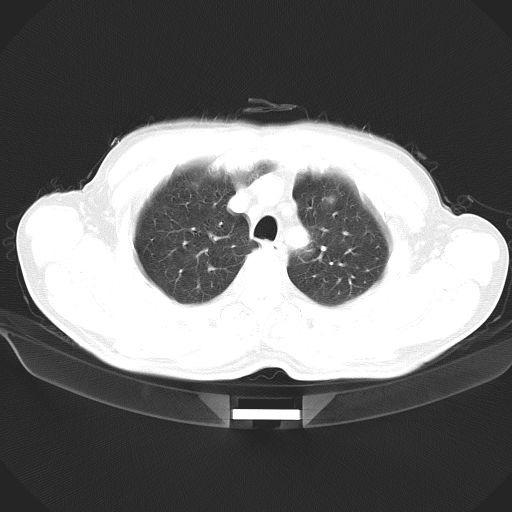

以下是引用心路寻觅在2010-3-1 10:23:00的发言:[br]1、考虑左肺上叶周围型肺癌[br]2、右上肺陈旧性病灶。[br][br][本贴已被 心路寻觅 于 2010-3-1 10:40:18 修改过]

以下是引用shuiyuan在2010-3-1 10:45:00的发言:[br]考虑左肺上叶中心型肺癌伴阻塞型炎症,邻近胸膜受侵。